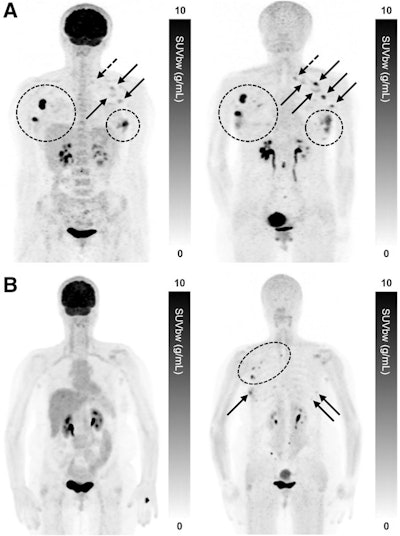

Maximum-intensity projection F-18 FDG-PET (left) and Ga-68 FAPI-PET (right) images of synchronous ILC. (A) A 42-year-old patient with multicentric primary lesions (encircled), regional (solid arrows), and distant inferior jugular lymph node (dashed arrows) seen on F-18 FDG-PET and subsequently confirmed on Ga-68 FAPI-PET, which also revealed additional malignant foci aligned with MRI. Some lesions exhibited high activity retention on Ga-68 FAPI-PET. (B) A 53-year-old patient showing no significant uptake on F-18 FDG-PET but synchronous bilateral lesions (arrows) on Ga-68 FAPI-PET, which also identified pathologic lymph nodes (encircled), resulting in upstaging. Image courtesy of the Journal of Nuclear Medicine.

An analysis by two experienced nuclear medicine physicians revealed that Ga-68 FAPI-PET/CT outperformed F-18 FDG-PET/CT, with higher radiotracer uptake in primary tumors (p = 0.001). Moreover, Ga-68 FAPI-PET/CT scans revealed more metastatic cancer in axillary lymph nodes and identified more lesions, including bone and liver metastases, according to the results.

The authors noted that F-18 FDG-PET/CT remains a highly valuable tool. Both approaches identified an identical number of primary breast lesions. Nonetheless, more accurate staging of patients with ILC may improve how they are treated, as current imaging approaches have higher rates of false negatives, they wrote.